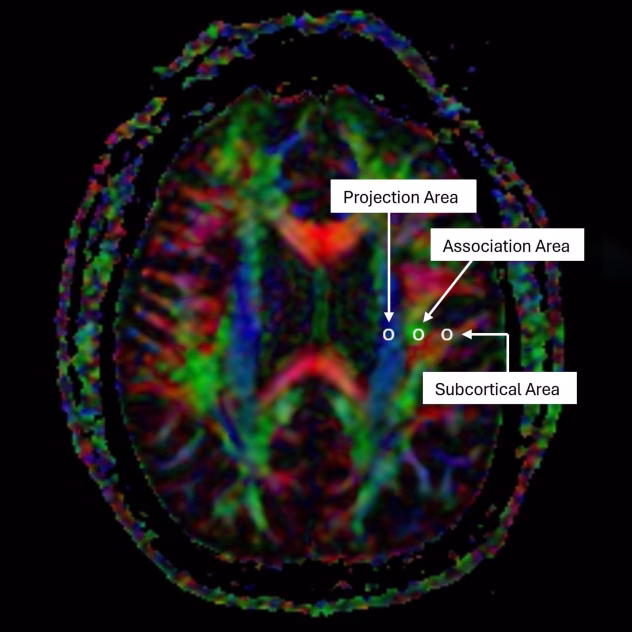

Tyrimui naudotas specialus magnetinio rezonanso metodas, vadinamas DTI ALPS. Jis seka vandens judėjimą aplink kraujagysles esančiose erdvėse, kurios tarnauja kaip drenažo keliai. Iš šių duomenų skaičiuojamas ALPS indeksas, leidžiantis neinvaziškai įvertinti glinfatinės sistemos veikimą.